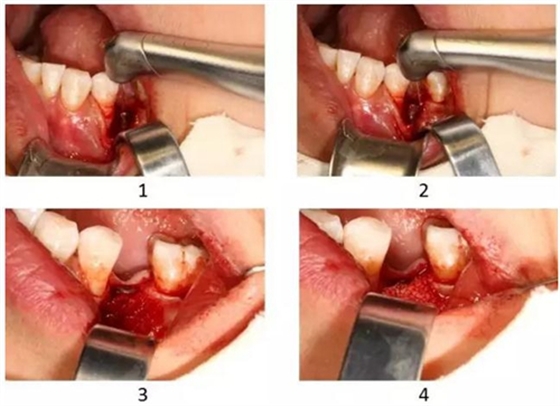

圖2-5-8 Er,Cr:YSGG輔助種植體周圍炎手術(shù)治療(GBR)

1.Er,Cr:YSGG輔助種植體表面去污

2. Er,Cr:YSGG輔助去除種植體周圍感染肉芽組織和骨組織

3. 種植體表面覆蓋自體骨

4. 植入骨代用品

5. 覆蓋屏障膜